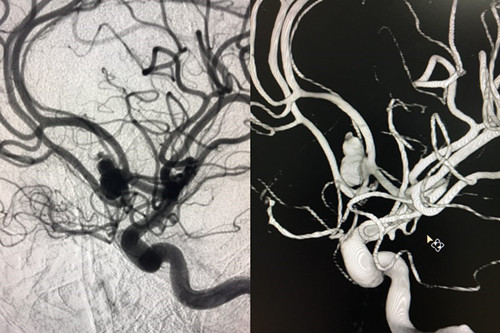

患者赵某,8月28日因“蛛网膜下腔出血”入住我院神经外科。入院时意识呈浅昏迷,且意识障碍进行性加重伴随右侧瞳孔散大,曲友直教授团队根据颅脑CT判定患者为动脉瘤引起的蛛网膜下腔出血。由于动脉瘤在人体内像个定时炸弹,随时会再次破裂,危险性非常大。能否及时为患者实施动脉瘤手术,避免动脉瘤继续破裂,从源头遏制患者病情继续恶化的可能性,直接关系到患者的预后。曲教授团队制定了详细的诊疗计划,在最短时间内为患者行侧脑室外引流术,并及时为患者实施了全脑血管造影,结果证实了术前判断,是大脑前交通动脉瘤,分上下两叶、宽颈。考虑到患者脑肿胀明显,基础状态差,急诊行开颅夹闭手术风险极高,曲友直教授团队反复评估、综合考虑后为患者实施了双导管技术宽颈动脉栓塞术。实施双导管技术避免支架辅助对前交通宽颈动脉瘤进行栓塞,术后患者无须长期口服抗血小板及抗凝药物、为患者术后赢得了进一步康复的机会、减少了长期服药的经济负担。手术过程十分顺利,术后患者病情稳定,正在进一步恢复治疗中。

术前造影

术中造影

术后造影